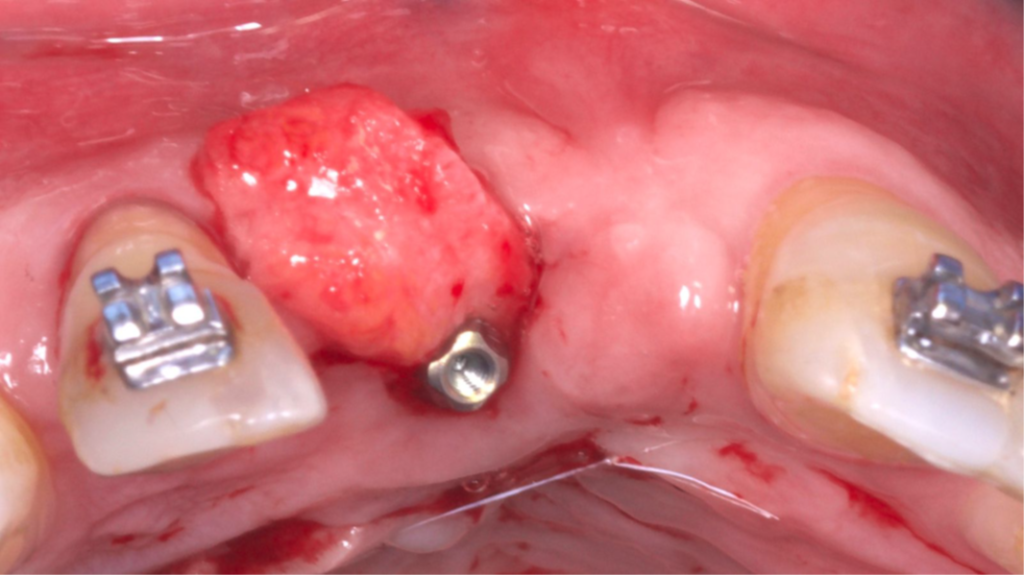

O tecido ósseo que suporta a estética rosa sofre diferentes modificações após uma extração e o biótipo gengival do paciente desempenha um papel importante na resolução multidisciplinar da instalação de um implante na zona estética. Uma alternativa viável de técnica para obter resultados estéticos e funcionais é a técnica VIP-CT (Vascularized Interpositional Periosteal Connective Tissue Flap).

O retalho VIP–CT, inicialmente idealizado para a proteção de enxertos em área anterior de maxila, pode também ser usado para aumento de rebordo na região anterior, apresentando benefícios em comparação com outras técnicas de enxertos de tecidos conjuntivos por obter um enxerto próximo ao leito receptor e completamente viável (por se manter com pedículo), bem como pode evitar a exposição de uma regeneração óssea guiada (ROG) ou enxertos ósseos de grande morbidade, como com a técnica de Khoury ou enxertos onlay.

Paciente do sexo masculino encaminhado pela Ortodontia para a instalação de um implante ao nível do dente 1.1 (Figura 1), com diastemas mésio-distais de 2mm, para utilização do implante como ancoragem absoluta e melhor andamento da movimentação ortodôntica.